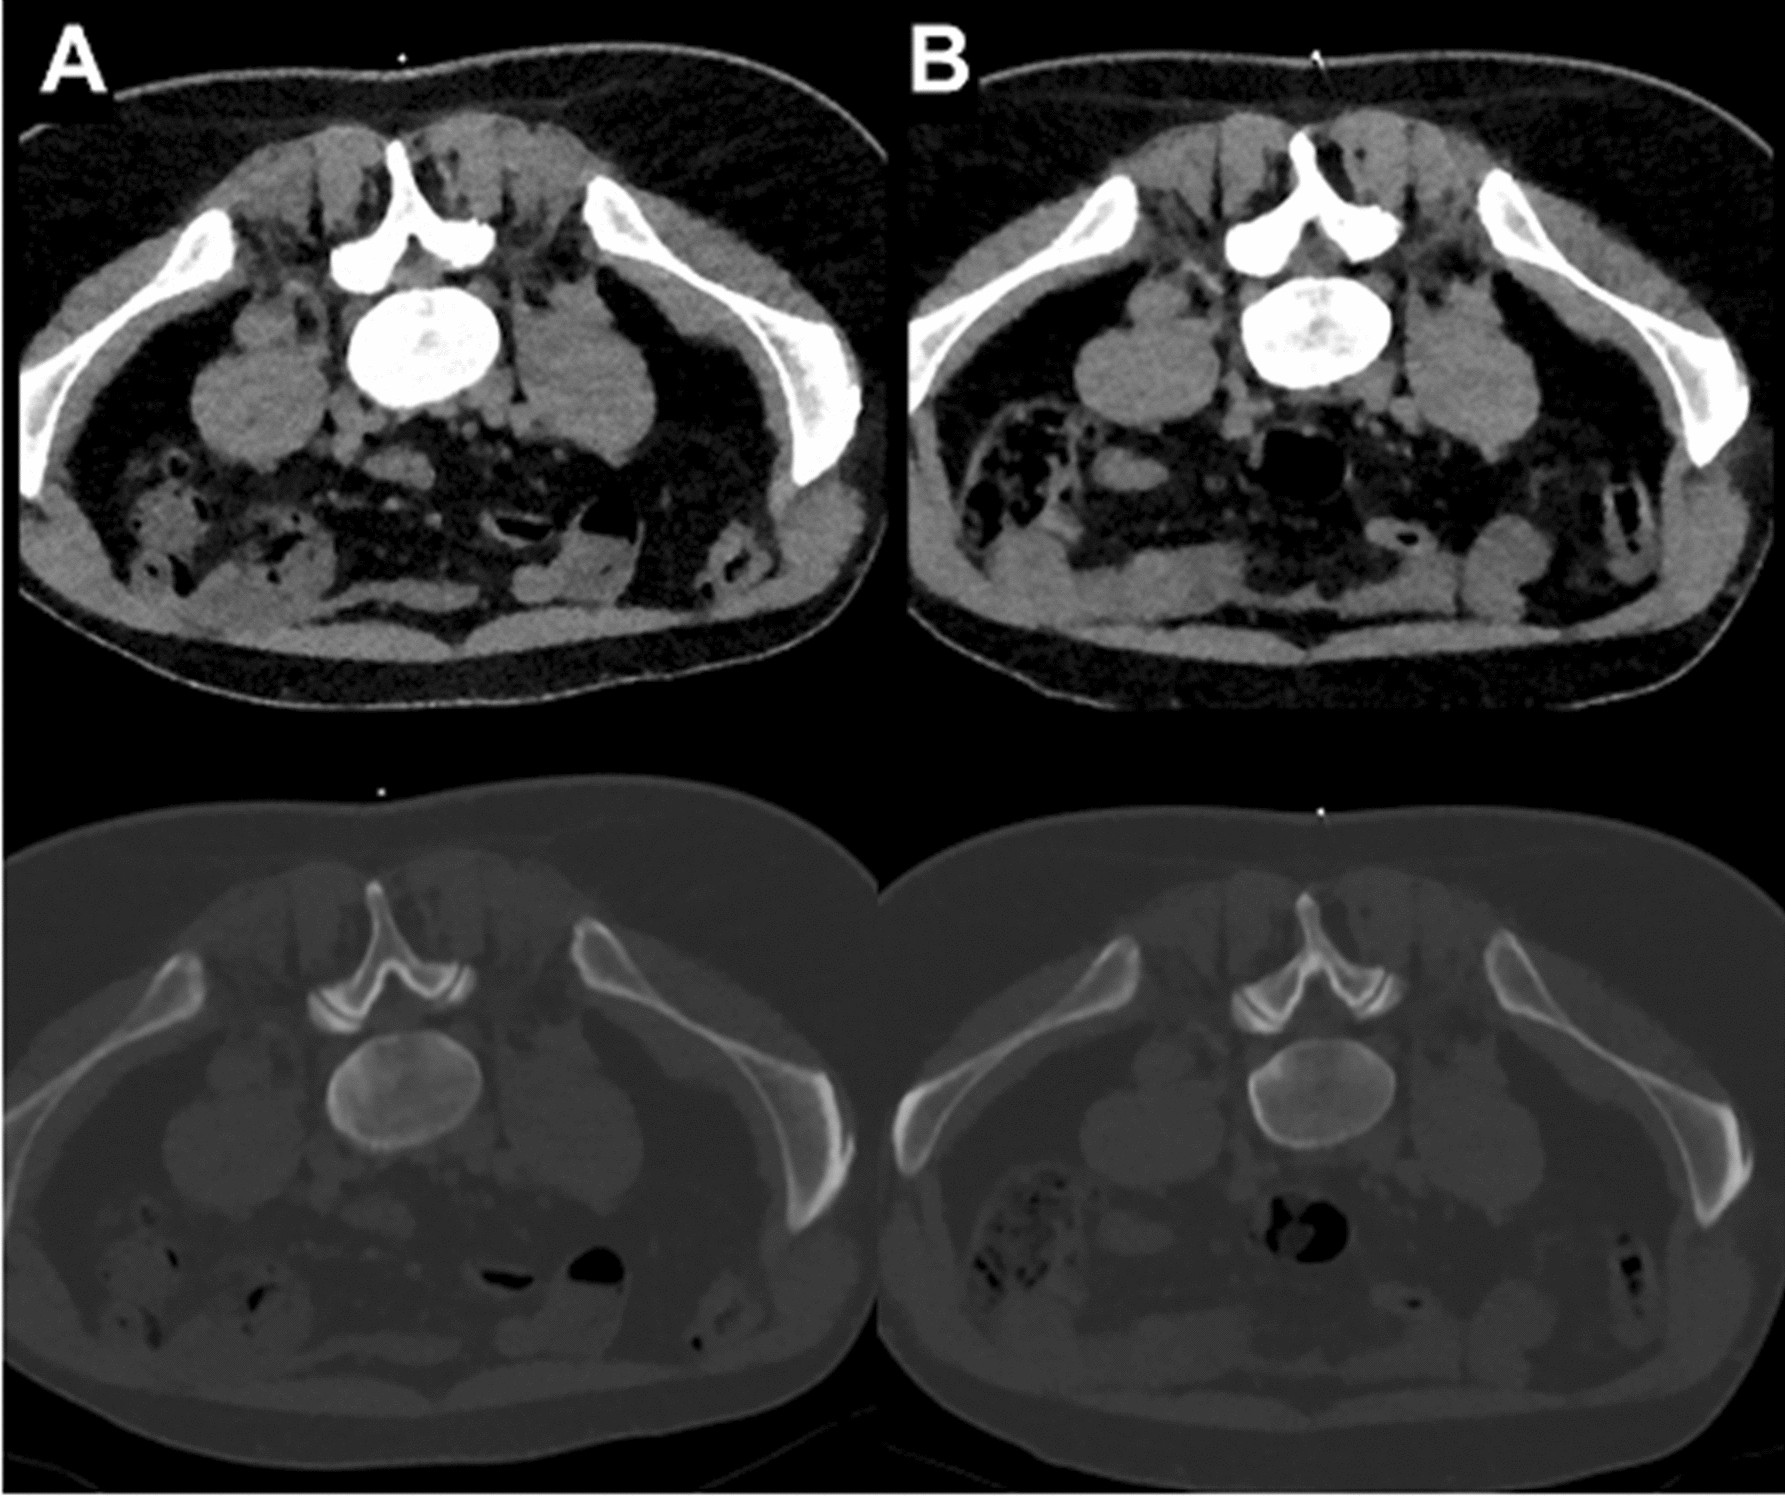

Figure 6

Examples for planning scans (bone and soft tissue windowing) of a right-sided L5 nerve root injection in a 42-year-old male with scanning at low dose (LD; A) and scanning with standard dose (SD; B). Acquisitions were performed 14 months apart from each other. Both scans were rated with excellent overall image quality and high confidence for intervention planning.